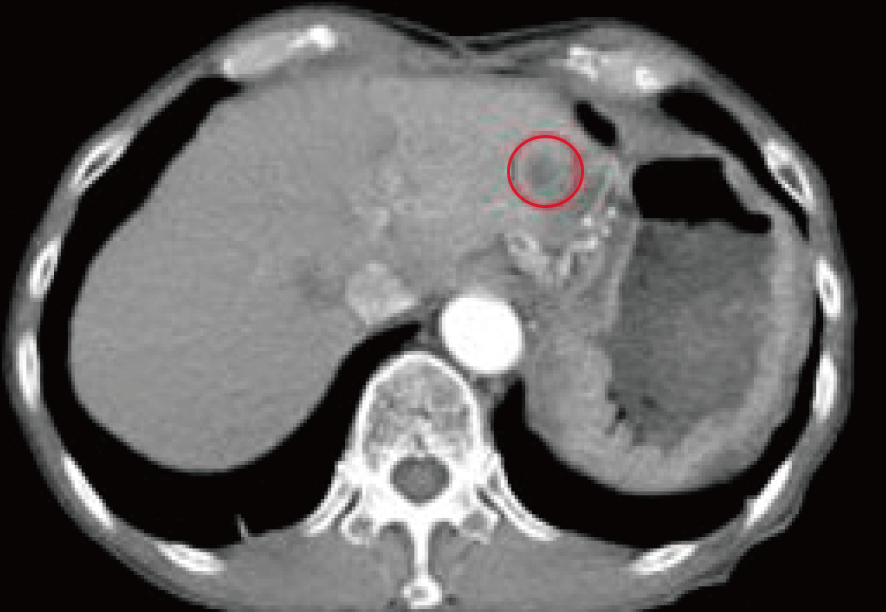

治療の開始後、およそ4カ月経過時点のCTを提示する。

画像上、肝臓に多発した転移がんは一カ所を除いて改善。

概ね縮小・共存関係に至ったと判断、引き続き経過観察を指示した。